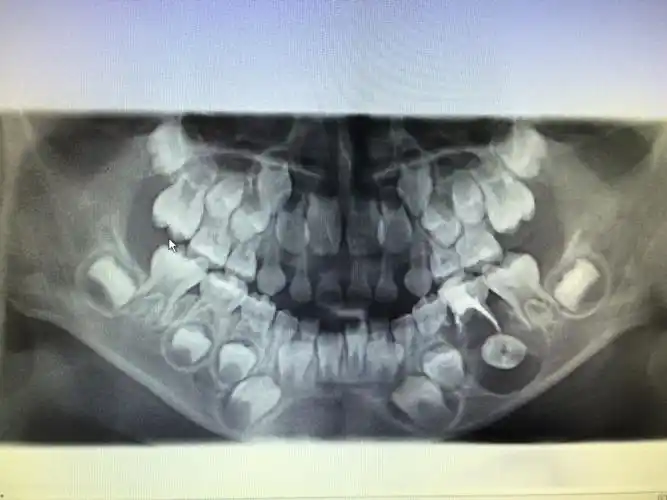

乳牙有哪些重要作用